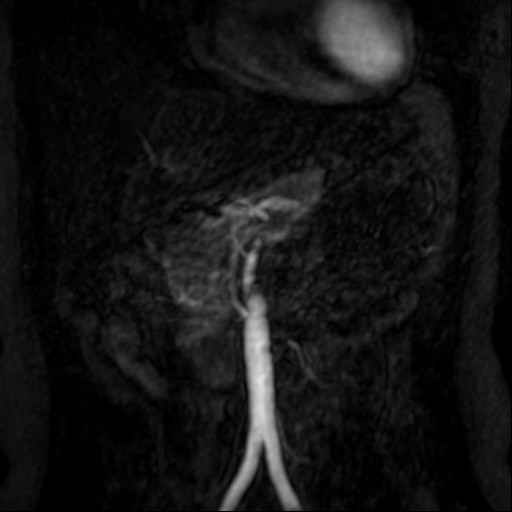

Angio abdominaal